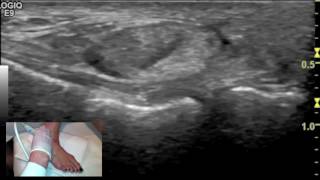

Ultrasound tutorial - Imaging of the Calcaneofibular Ligament

This video demonstrates the technique used to image the calcaneofibular ligament of the ankle. Normal ultrasound images are shown concurrently. www.eastriverimaging.com